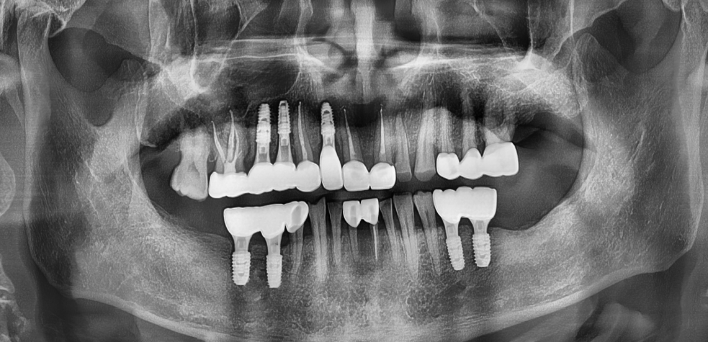

Before Before

2020.02.30

After After

※ 더서울치과의원은 의료법을 준수하며 위 케이스는 실제 환자의 동의를 얻은 사례로 치료 전, 후가 동일한 환경에서 촬영되었습니다.

환자 케이스에 따라 부작용이 발생할 수 있습니다. 이 부분은 의료진의 충분한 상담과 체크를 통해 예방하고 줄일 수 있습니다.

[임플란트 부작용] 수술 후 관리가 소홀할 경우 출혈, 주위염 등의 부작용이 발생할 수 있어 구강 위생을 철저히 유지하고, 정기적인 검진을 통해 상태를 점검하는 것이 중요합니다.

환자 특징

환자 특징01무치악 상태

환자 특징02수년간 무치악으로 지내심

임플란트가 불가능할것이라

생각하고 내원

위, 아래 6개씩 식립

디지털 풀아치 임플란트